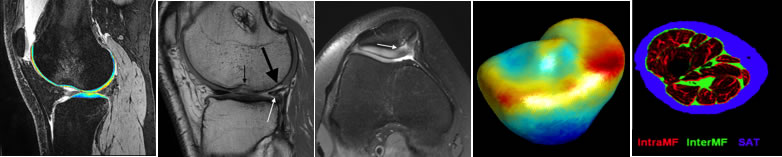

PAMI is developing novel imaging acquisition and image post-processing techniques and clinical translation to improve patient care. Specifically, we focus on developing rapid, reliable, quantitative imaging techniques that can provide novel imaging biomarkers for early diagnosis and prognosis for musculoskeletal disorders. We are also exploring cutting-edge, deep-learning techniques for fast imaging acquisition, automatic tissue quantification and clinical outcome prediction.

We have developed algorithms combining an advanced CS based reconstruction technique, LAISD, and an advanced parallel imaging technique, JSENSE, and achieved superior quantitative accuracy for T1ρ quantification with AF up to 4. We will further develop model-based CS techniques to take full advantage of the known quantitative model for T1ρ and T2 decay such that the estimated T1ρ and T2 maps are more robust to noise. We are also working on develop novel MR reconstruction algorithm using deep learning techniques. Compared to CS, one advantage of machine learning methods is the fast image reconstruction. With a 15-layer convolutional neural network (CNN), we have reduced the acquisition time 6 times without significantly affecting the image quality, as well as clinical grading and diagnostic capability. We are currently working on developing DL reconstruction algorithm for cartilage relaxation time quantification, for both mono- and bi-exponential decay components.

Automatic Tissue/Lesion Segmentation Using Deep Learning Techniques

We have developed deep learnings models for knee joint anatomy segmentation on MRIs based on the recent development of the conditional generative adversarial networks (cGAN) and U-Net. Trained and tested on the osteoarthritis initiative (OAI) data, our model is able to perform multi-class segmentation for patellar cartilage, femoral cartilage, lateral/medial tibial cartilage, lateral/medial meniscus simultaneously with superior performance compared to state-of-the-arts models. We will further deploy our automated segmentation model for other knee tissues such as ligaments and bones, and extend to other joints. Furthermore, we will adopt transfer learning for improved model efficiency and accuracy to apply our model to clinical settings with different MRI sequences and platforms (1.5T and 3T). Deep learning models for automatic abnormality detection (for example, bone marrow edema and synovisit) and clinical outcomes prediction will also be developed.